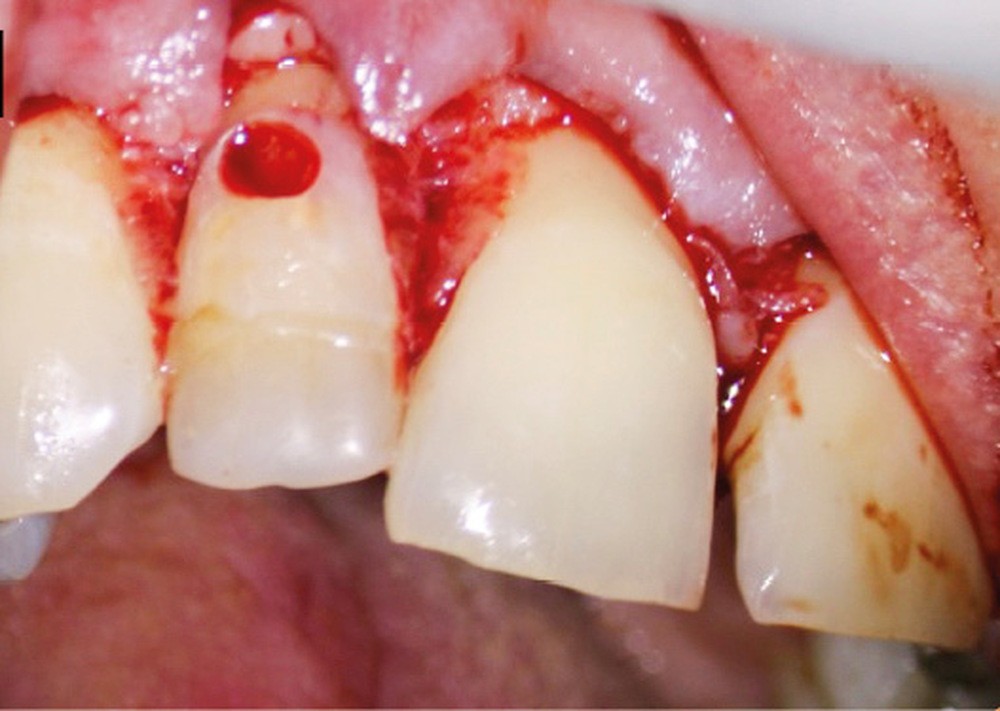

Ce type de perforation est également la plupart du temps iatrogénique et survient lors de la recherche ou de la mise en forme canalaire, lors de la préparation pour un logement de tenon radiculaire. Situées au niveau du plancher pulpaire des dents pluriradiculées, ou au niveau des entrées canalaires des dents monoradiculées ou pluriradiculées, il s’agit le plus souvent de perforations à quatre parois. Si la perforation survient en cours de traitement, elle doit être gérée immédiatement pour un meilleur pronostic (fig. 4). Néanmoins, il est important de prendre en compte l’épaisseur résiduelle du plancher. Si le plancher est trop fin, il ne sera pas possible d’envisager de traiter la perforation.